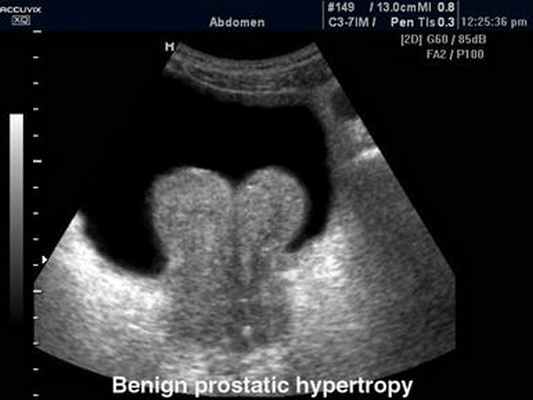

в выявлении патологических изменений надпочечников и предстательной железы –

гиперплазии, воспалительных изменений, кист и опухолей. УЗИ мошонки позволяет детально

изучить состояние яичка, его придатков и семенного канатика.

Для УЗИ предстательной железы (простаты) могут использоваться датчики, вводимые

в прямую кишку. Непосредственная близость от простаты позволяет более точно изучить

морфологию ткани железы и семенных пузырьков.

В связи с большой распространенностью аденомы и рака предстательной

железы рекомендуется проводить ее УЗИ мужчинам старше 50 лет при недержании

мочи, учащенном либо замедленном мочеиспускании, ослаблении напора струи мочи,

ночных позывах к мочеиспусканию.

Доброкачественная гиперплазия предстательной железы.